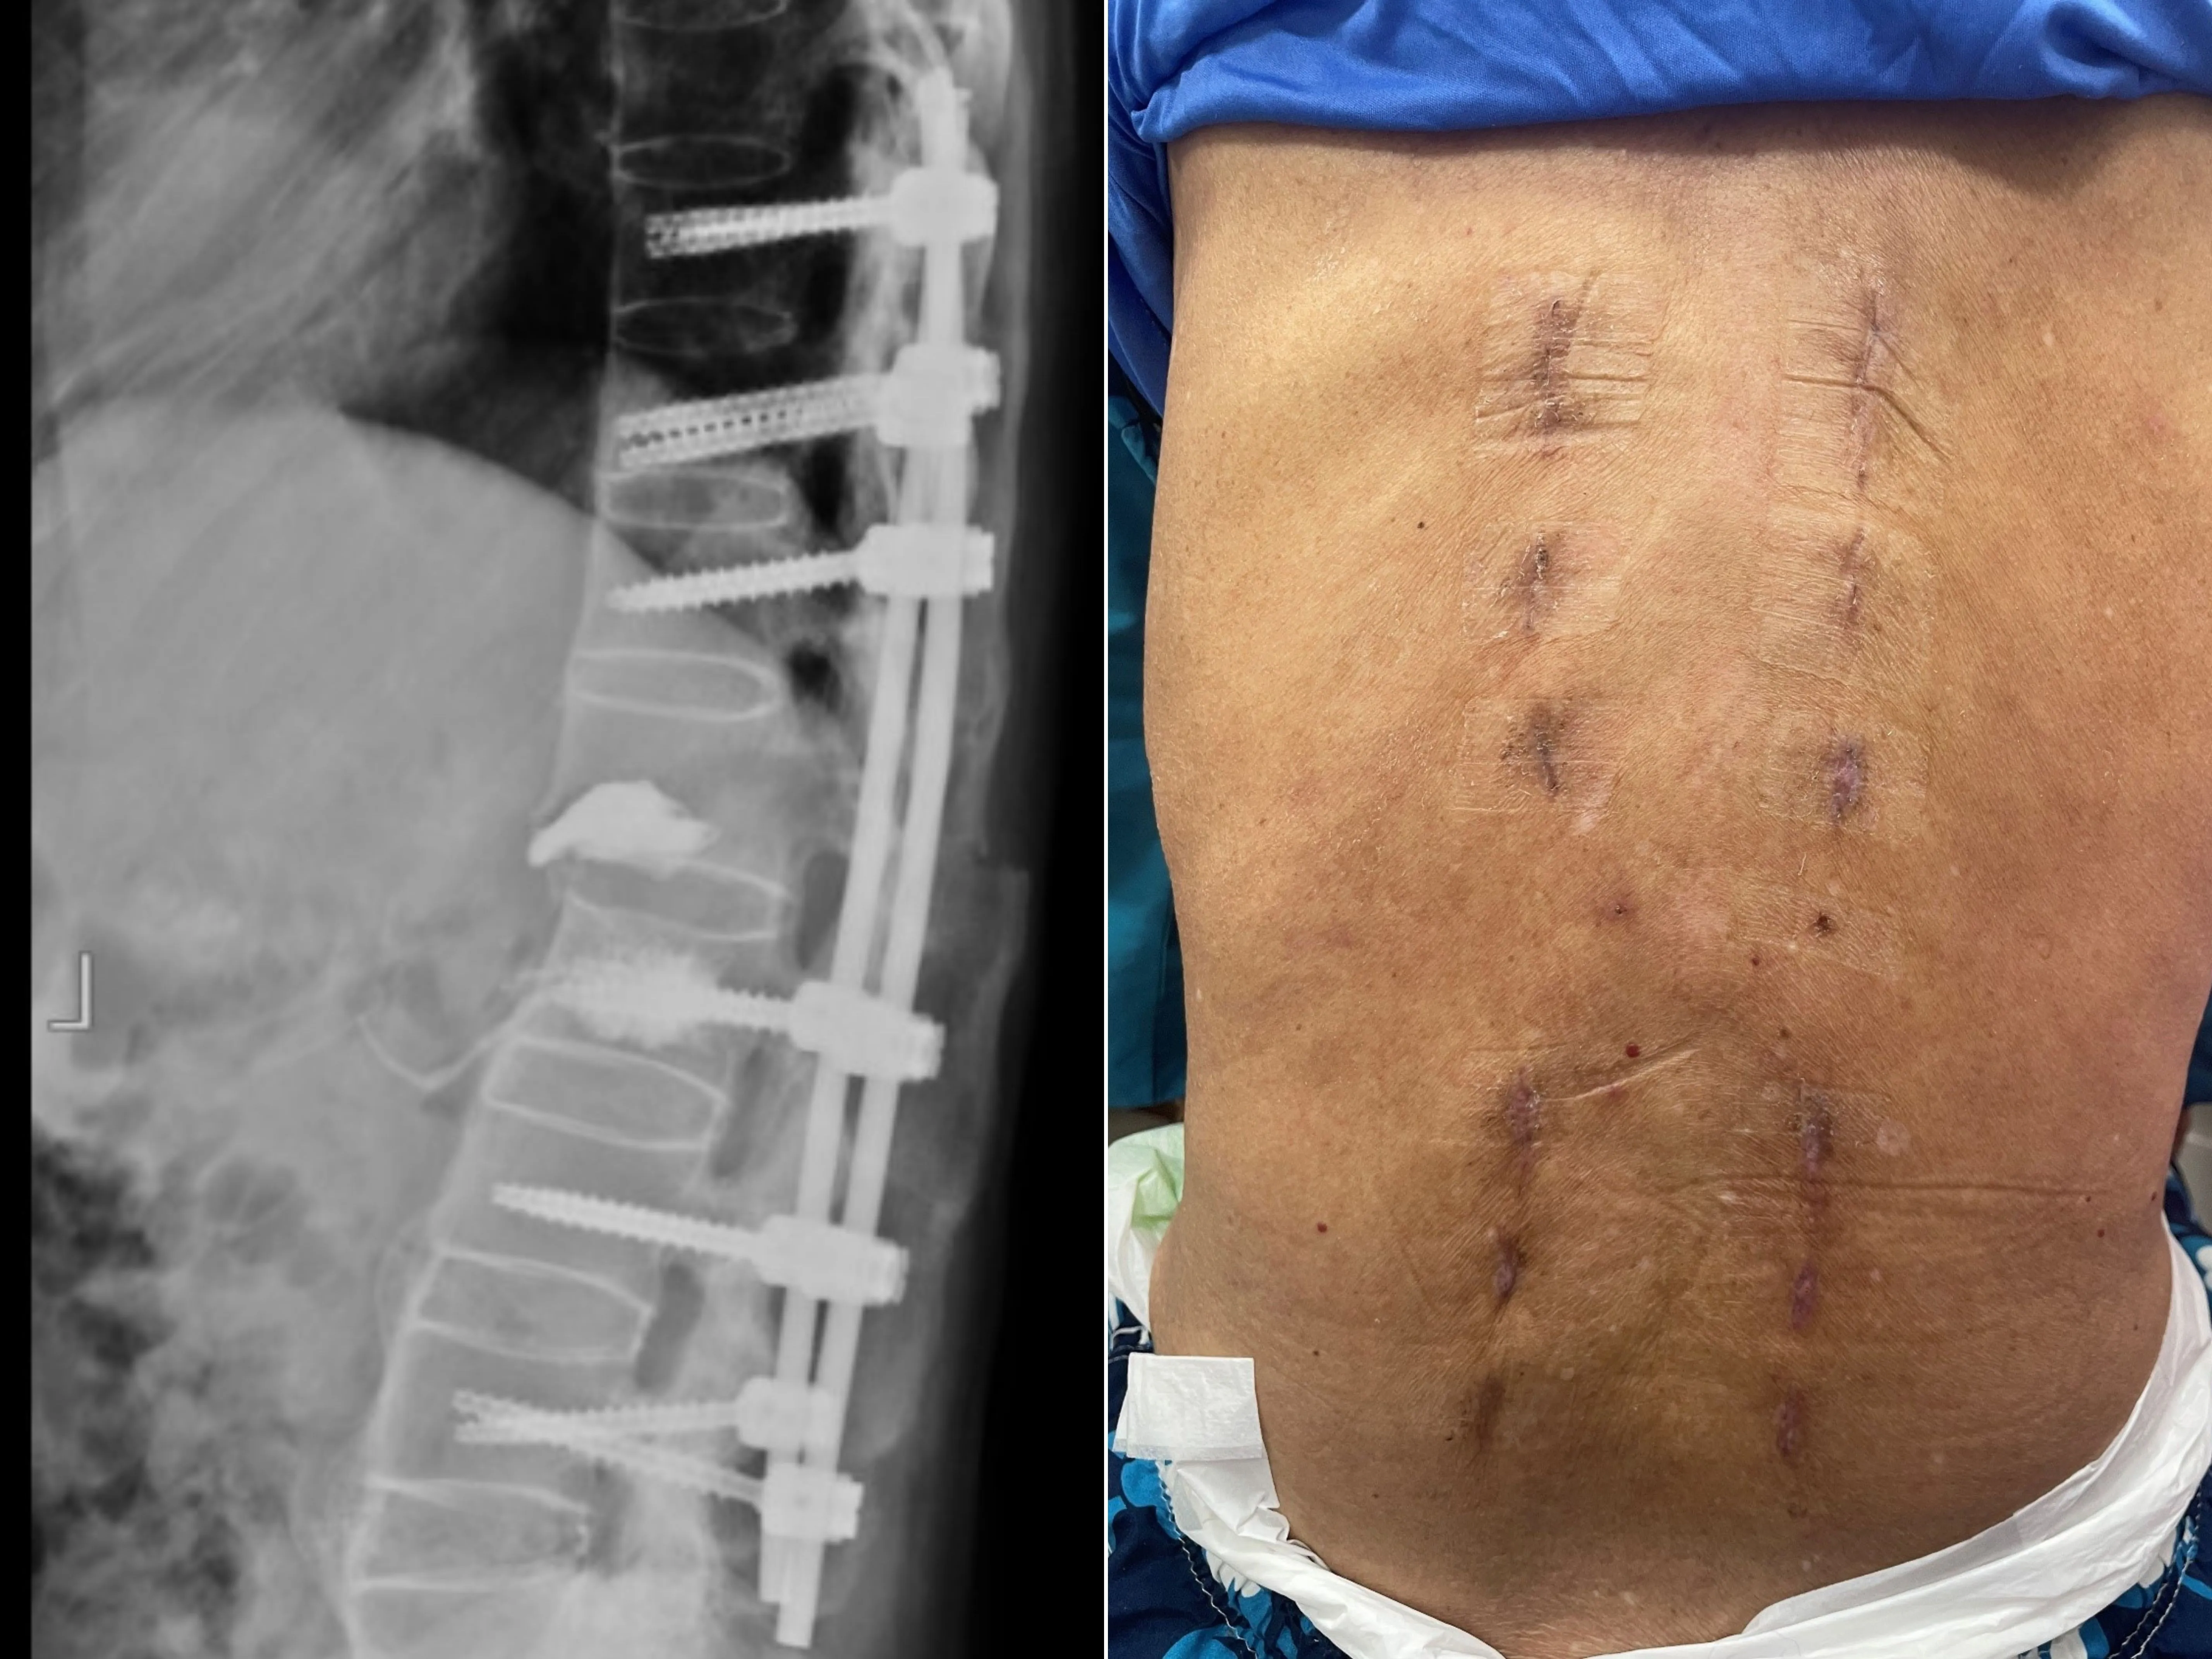

幸運的是,張先生並未出現神經壓迫症狀,下肢肌肉力量與知覺皆正常。考量到脊椎不穩定的危險性,喻醫師迅速幫張先生安排從胸椎第十節到腰椎第四節的微創脊椎固定手術。相較傳統手術,微創手術僅需在脊椎釘入口處開小傷口,最大程度保留肌肉及周邊組織。此外,手術中也搭配了電腦斷層導航系統,提高手術精準度及縮短手術時間,不僅能大幅減輕術後疼痛,也讓患者恢復速度更快。

病人術後照。